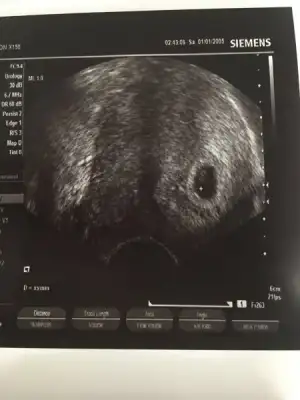

Kızlar kesemizi gördük bugün❤️2 kese görünüyor dedi doktor. Birinin içinde mercimek kadar belli, diğer kese flu dedi. Haftaya kadar gelişebilir de, tek gebeliğe dönebilir de dedi.

Gittik kuzumm. 2 kese görünüyor dedi doktor. Birinin içinde mercimek kadar belli, diğer kese flu dedi. Haftaya kadar gelişebilir de, tek gebeliğe dönebilir de dedi.